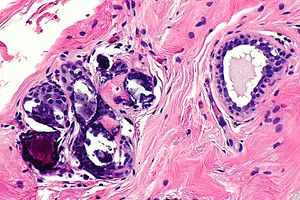

Calcification in benign breast tissue. H&E stain. (WC/Nephron)

Breast calcifications may be found in benign or malignant breast specimens.

• Purple globs (with concentric rings) on H&E - represent calcium phosphate.

• Often in the lumen of a gland, may be in the stroma.

• Calcific material typically has a well-demarcated border +/- "sharp corners".